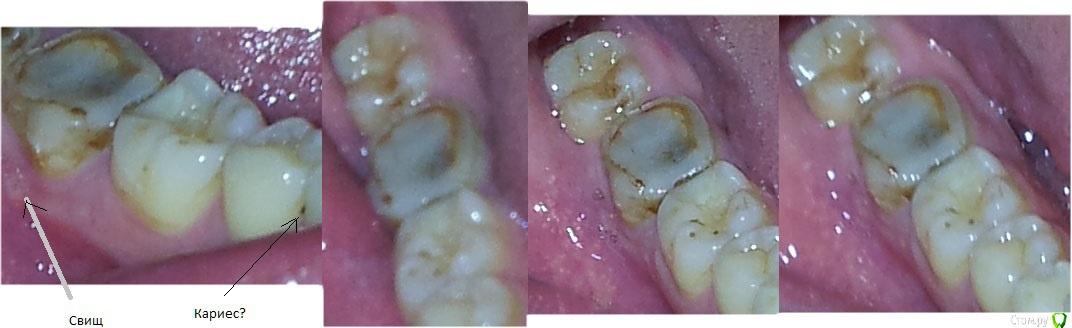

isubru Опубликовано 1 ноября, 2015 Автор Поделиться Опубликовано 1 ноября, 2015 Фото многострадального зуба. Видно потемнение коронки и свищ на десне. Ссылка на комментарий